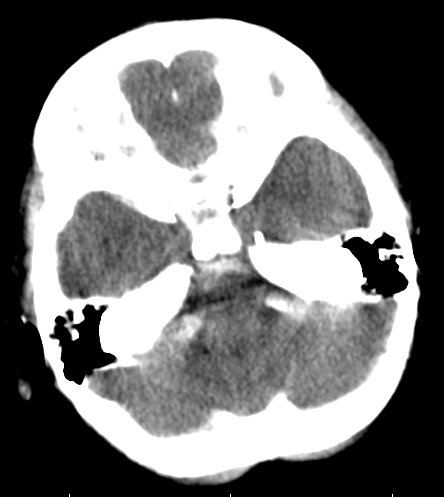

女,3岁,头部外伤一小时。半卵圆中心低密度是什么意思,病灶?侧脑室?请指教。

正常表现

幼儿正常脑白质表现,长期观察,必要时mr

从层面看不是侧脑室,考虑低密度变,建议mri。

不是侧脑室,考虑正常脑白质。为慎重,建议mr!